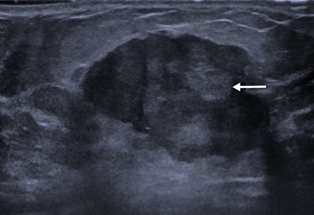

Figure 1 Ultrasound image of the right breast showing a mixed solid cystic lesion with microlobulated border at the retro-areolar region.

A 72 years old gentleman presented to our centre in 2019 with the right breast swelling and painless nipple bloody discharge for the past three months. He claimed the swelling was progressively increasing in size with changes noted on the surface of the nipple skin. The patient also had constitutional symptoms such as loss of weight and loss of appetite for the past one year. He claimed he lost about 10kgs in the last 6 months. Otherwise, the patient denies having any family history of breast cancer nor consumed any kinds of hormonal pills or supplements. Triple assessment was done on the patient and clinical examination revealed a hard, non-tender lump at the retro areolar region measuring about (2x1) cm. There were blood and serous discharge from the nipple. No mass was palpable on the other region of the breast or contralateral side. Bilateral axillary lymph nodes were not palpable. Initial right breast ultrasound noted the presence of cystic and solid lump at the retro areolar region measuring (1x1x1.8) cm. Also noted was internal vascularity with a layer of sediment within the cystic mass. The imaging findings were categorized as BIRADS 4.We then proceed with computed tomography (CT) scan and noted the presence of a focal enhancing retro areolar lesion on the right breast measuring (0.8x0.8x1.0) cm with no extension to the underlying structures. There were some sub-centimetres bilateral axillary lymph nodes with preserved fatty hilum with largest was 0.9cm in the right axilla. Ultrasound-guided biopsy was performed and was confirmed to be of intra-ductal papillary carcinoma in origin. The patient was staged as T1N0M1 according to the TNM classification. The patient was arranged for a right mastectomy the following week. He was then discharged home well after a week and a surveillance mammogram was performed a year later and no focal lesion seen on the left breast (Figure 1 & 2).